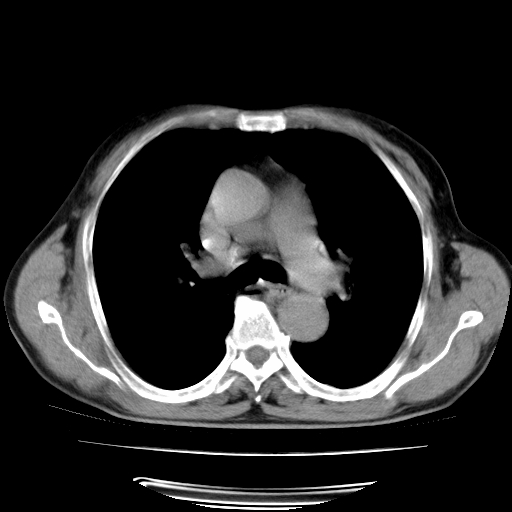

男,71岁,咳嗽,气喘10年,再发并咯血.胸片见气胸

考虑  左肺中心型肺癌伴阻塞性肺炎,肺不张,纵膈淋巴结肿大。慢支炎,肺气肿,左侧气胸肺压缩5%

左侧中央型肺癌伴纵膈淋巴结转移。

左肺中心型肺癌伴阻塞性肺炎,肺不张,纵膈淋巴结肿大

1)考虑左肺中心型肺癌伴阻塞性肺炎、左肺下叶肺不张、左侧肺气肿,纵膈淋巴结转移。2)左侧气胸(肺组织压缩约5%)。

左肺中心型肺癌伴阻塞性肺不张、肺气肿 。

1)考虑左肺中心型肺癌伴阻塞性肺炎、左肺下叶肺不张、左侧肺气肿,纵膈淋巴结转移。2)左侧气胸。